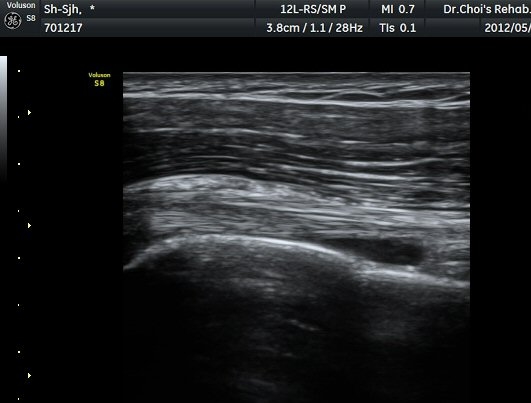

Á߸³»óÅ ¾î±ú ¾Õ Ⱦ´Ü¸é°Ë»ç¿¡¼­ À̺ειڱ٠ÁÖÀ§¿¡ ¼ö¾×Àú·ù°¡ °üÂûµÇ°í(»çÁø 1) ÆÄ¿öµµÇ÷¯

°Ë»ç¿¡¼­ Ç÷·ùÁõ°¡°¡ °üÂûµÈ´Ù(»çÁø 2). À̵ιڱ٠Á¾´Ü¸é°Ë»ç¿¡¼­µµ °Ç ÁÖÀ§ ¼ö¾×Àú·ù°¡ È®ÀÎ